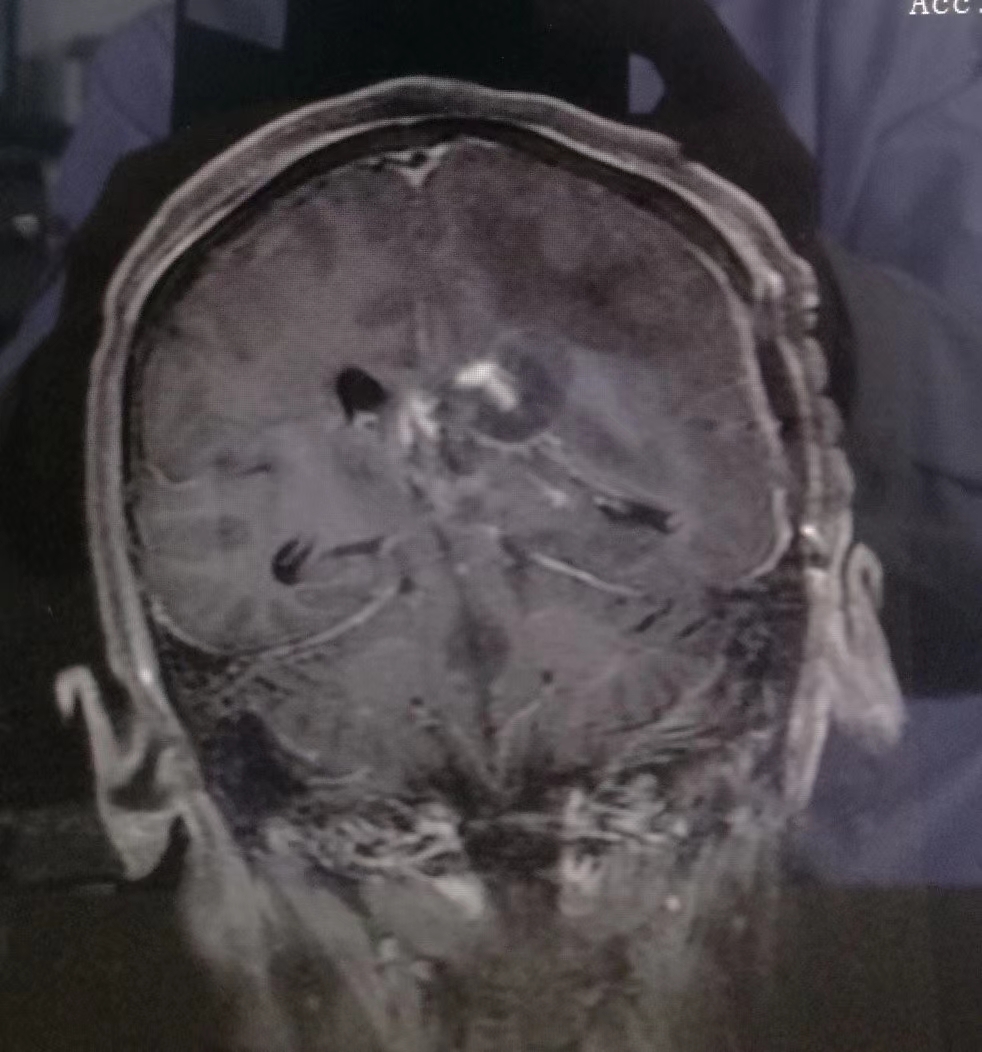

术前MRI